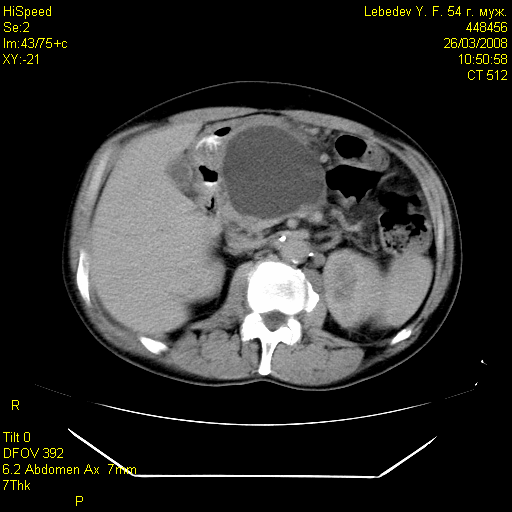

Среди обследованных 98 больных, объем некроза более 50% (субтотально-тотальный панкреонекроз) был обнаружен у 34 (34,7%), в т.ч. в основной группе у 16 (32,0%), а контрольной группе у 18 (37,5%) пациентов (рис.3).

Рис. 3 Рис. 4.

Больной Р. Больной Л.

КТ картина тотального геморрагического КТ картина постнекротической кисты

панкреонекроза, парапанкреатита, параколита. головки поджелудочной железы.

Объем некроза в пределах 30-50% выявлен у 42 (42,9%), а объем некроза менее 30% был отмечен у 22 (22,4%) пациентов. С помощью КТ нам удавалось установить локализацию, размеры и толщину стенок постнекротических кист поджелудочной железы (рис.4)